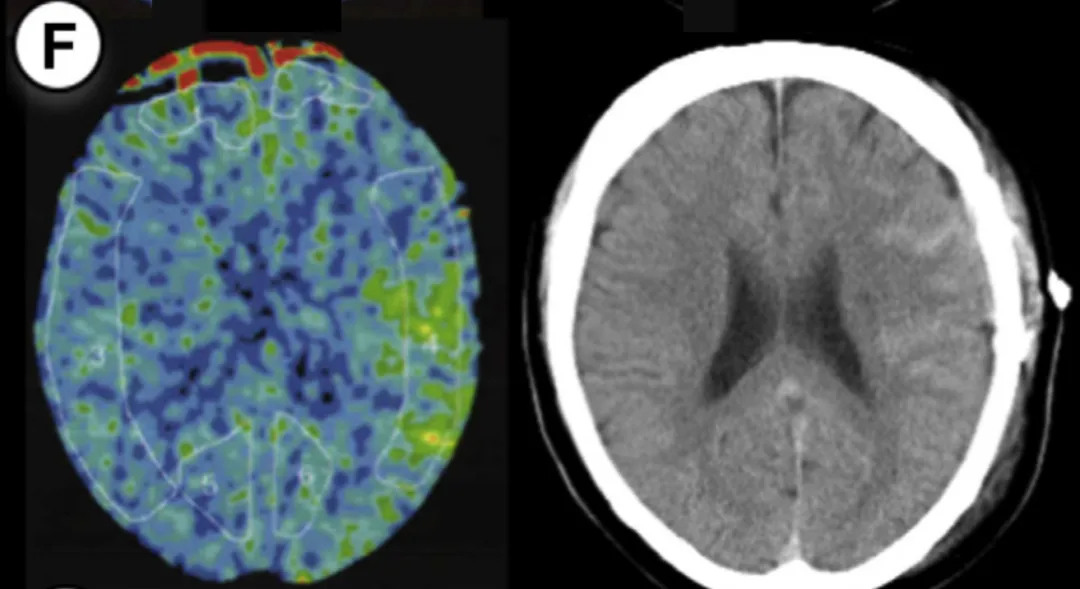

病例6

26岁男性,有TIA病史,行右侧大脑手术。方法1 rCBF增加率63%,方法2达72%。术后第2天发现硬膜下血肿合并蛛网膜下腔出血,经1天镇静后出血吸收。

7例病例年龄范围25-55岁,出血类型包括脑出血(ICH)、蛛网膜下腔出血(SAH)、硬膜下血肿(SDH)及混合出血,发病时间集中于术后1-5天。所有病例rCBF增加率均超过阈值,证实了预警系统的可靠性。

通过氙气增强CT,在大脑中动脉供血区固定部位测量rCBF,术后即时完成首次检测。

低风险(方法1<30%、方法2<50%):短期镇静+常规控压

中风险(方法1 30%-100%、方法2 50%-100%):持续镇静24-30小时+严格控压

极高风险(≥100%):镇静36小时以上+多次复查